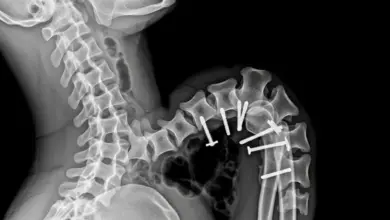

O critério mais usado no raio X é o ângulo de Cobb. Considera-se escoliose quando esse ângulo mede 10° ou mais.

A cirurgia pode ser indicada em curvas graves, com progressão, desequilíbrio importante, dor refratária ou risco funcional.

É uma cirurgia grande, com tempo operatório longo, risco de sangramento, infecção e complicações neurológicas, como em qualquer procedimento complexo de coluna.